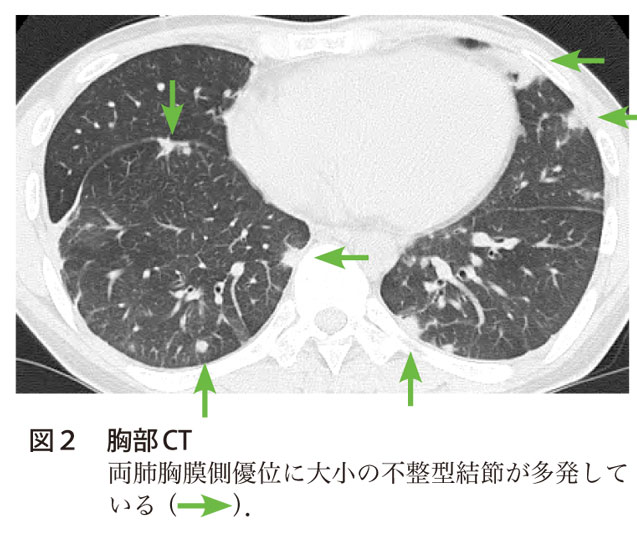

化膿性関節炎から敗血症性肺塞栓症を発症した1例 呼吸と循環 55巻11号 医書 Jp